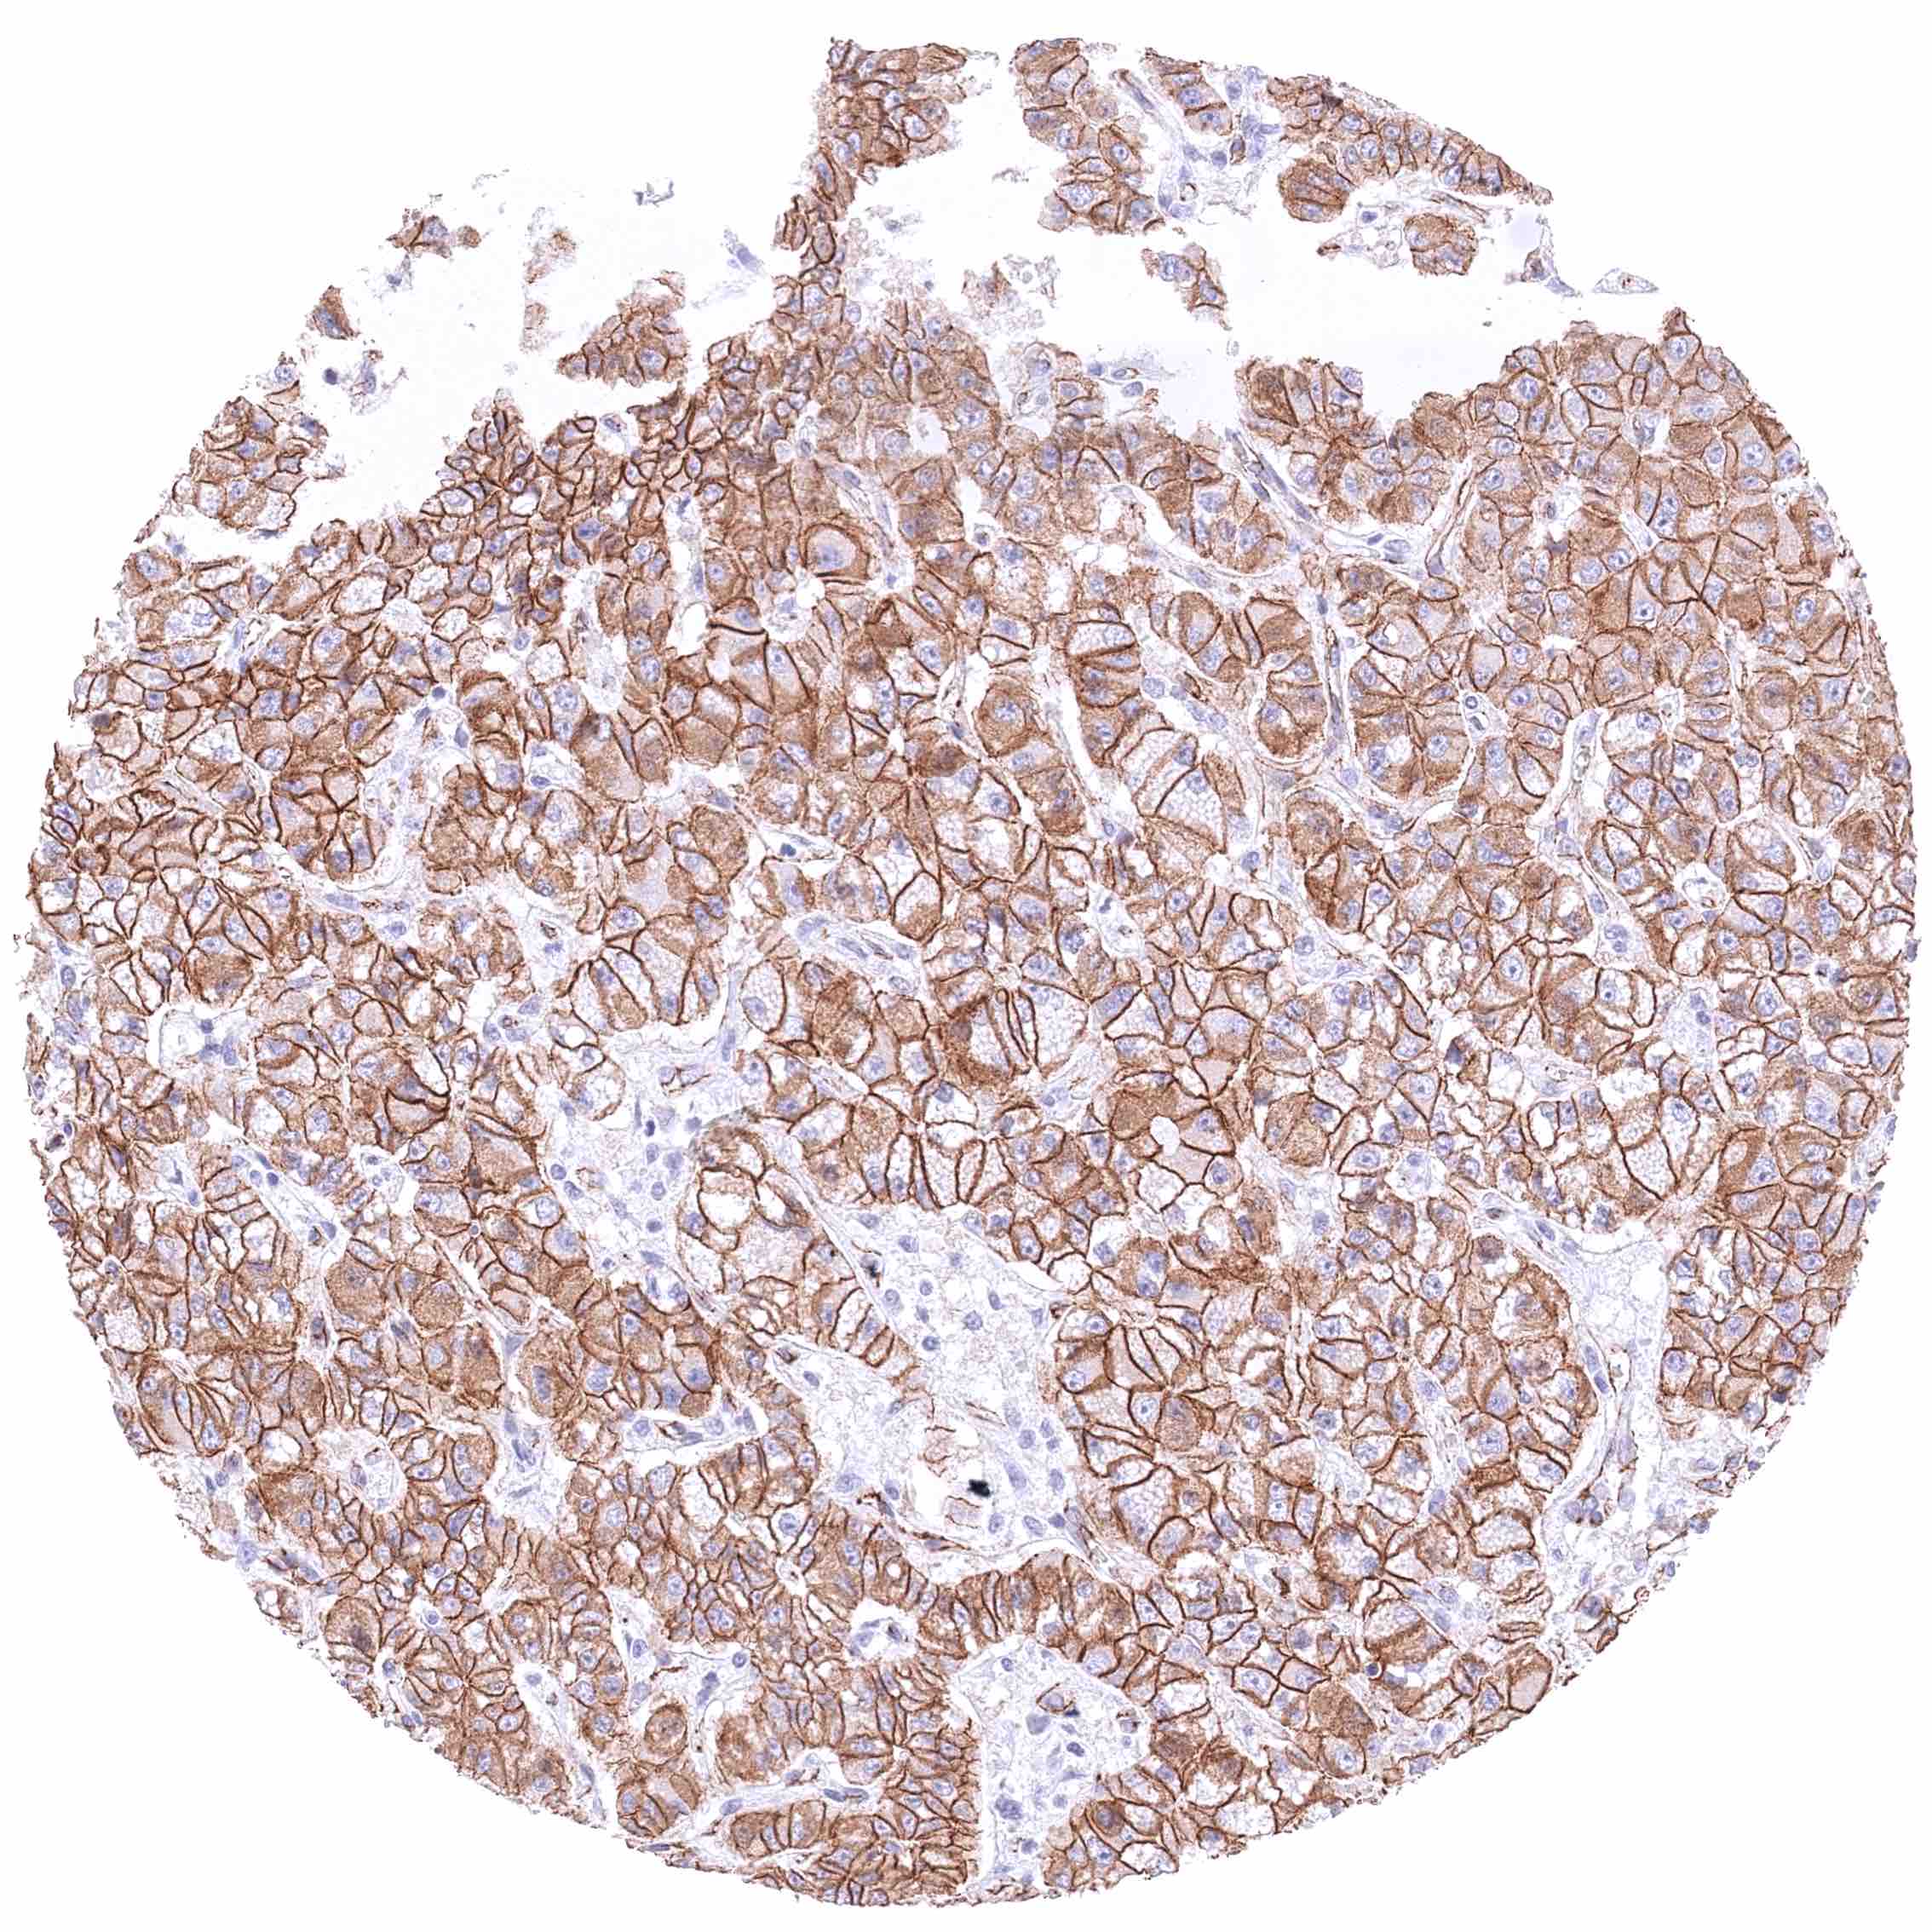

Kidney – Chromophobe renal cell carcinoma with a moderate to strong β-Catenin staining of tumor cells.